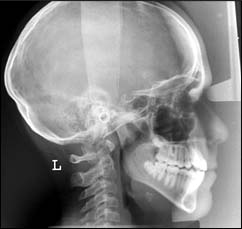

Téléradiographie de profil et de face

Ces examens sont principalement réalisés dans le cadre d’un traitement ODF ; ils ont pour but de permettre un diagnostic et un pronostic précis pour entreprendre un traitement.